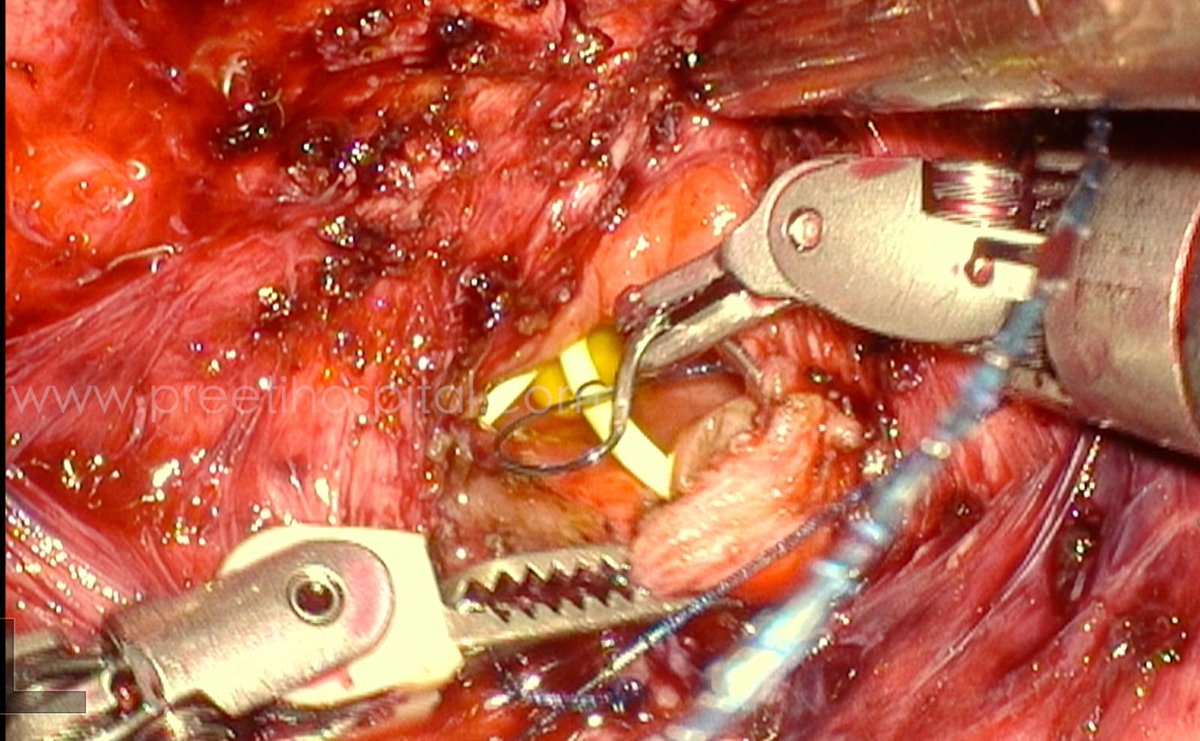

A 7-year-old male child diagnosed at age 3 years with recurrent UTIs had a left-sided congenital megaureter and diverticulum and right side reflux and small diverticulum. At age 3 We did   only  left-sided laparoscopic tapering ureteric reimplantation and diverticulecomy. Four